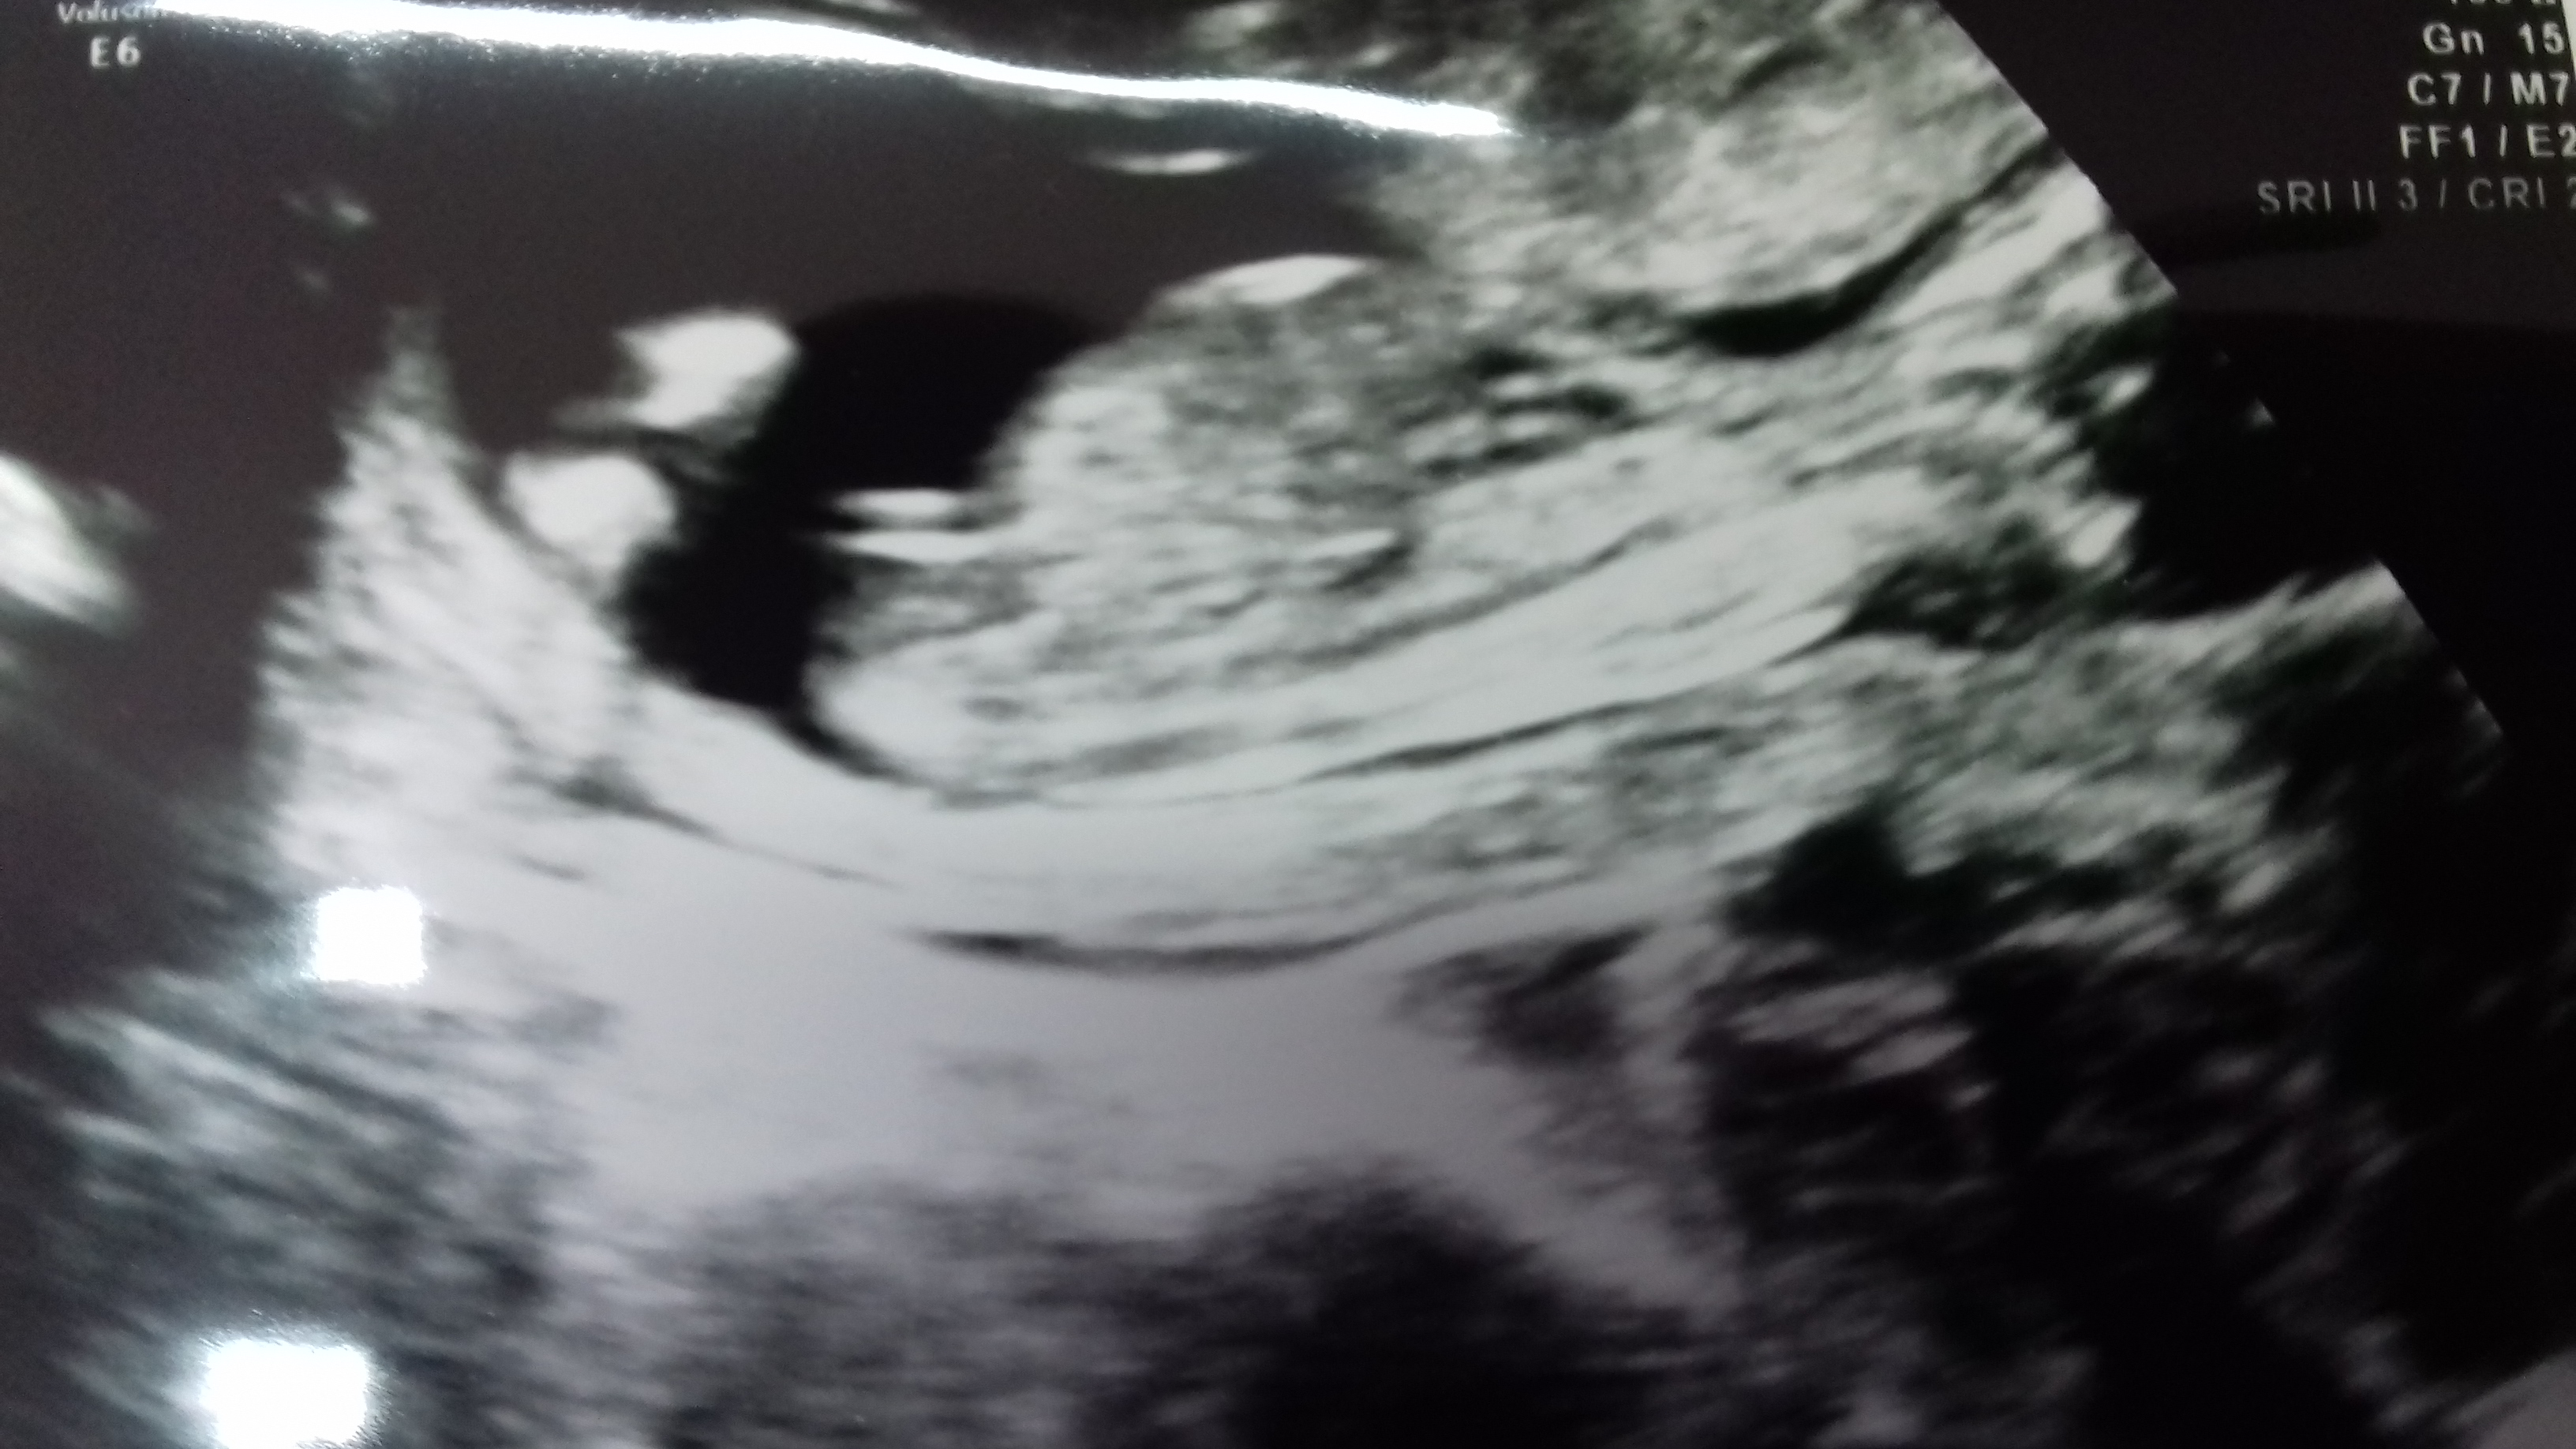

Girl!!

Tricky, leaning boy. Do you have a video?

Not 100% sure, but I'm leaning boy.

In sorry but i think thats a boy!

Leaning boy too from pic 1, hope I'm wrong!!:)

Tricky nub, this last pic could be girly. The reason why I guessed boy is because the nub appears to be at an angle in the other pics. So this one could go either way IMO.

Yes, this one:) To me it looks like the top line isn't fully attached and the bit attaching it possibly is more of a shadow or blurred bit, so the remaining bit looks like a possible blue angled nub, the lines are also quite thick which makes me lean a little to the blue side aswell, I am often wrong on these though;) Often!:)